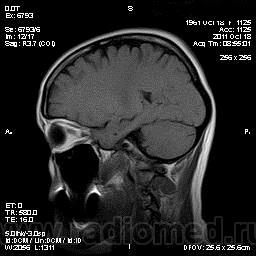

S-образный ход зрительных нервов

S-образный ход зрительных нервов с двух сторон. Жалоб на зрение нет.

Случайная находка при исследовании головного мозга по поводу головных болей около 6 лет,

головокружения, слабости. В июне этого года было ДТП - ударялась головой

Зачастую как признак в/черепной гипертензии, при головных болях, следует искать проляпс хрительного нерва, уплощенность глазного яблока + формируещееся/сфоримрованное пустое турецкое седло.. если есть 2 и более признаков то высока вероятность в/черепной гипертензии..

И не только седло. Признаков много. Тут и седло есть и извитость нервов + расширение их САП.